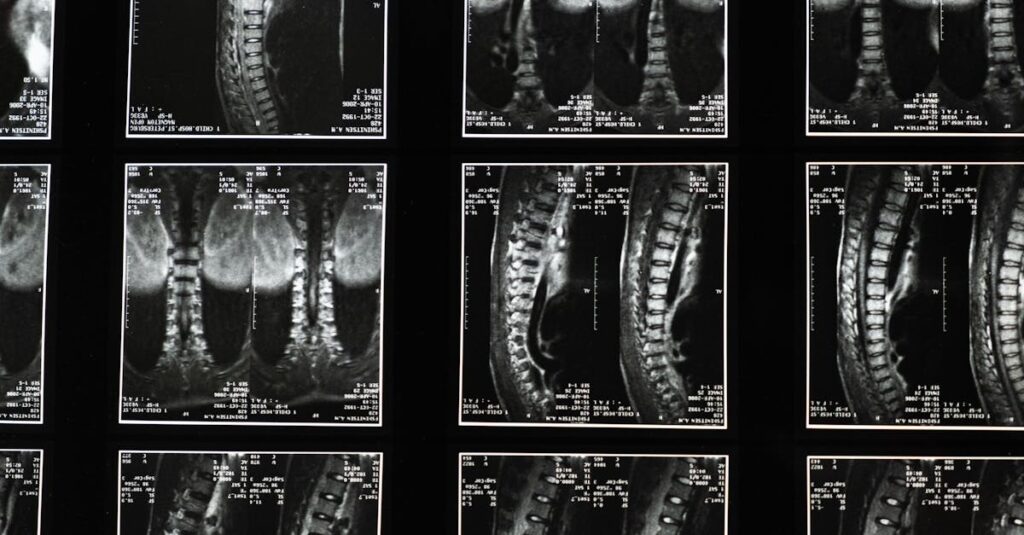

Une IRM ou une radiographie est généralement nécessaire pour confirmer la cause de la sciatique.